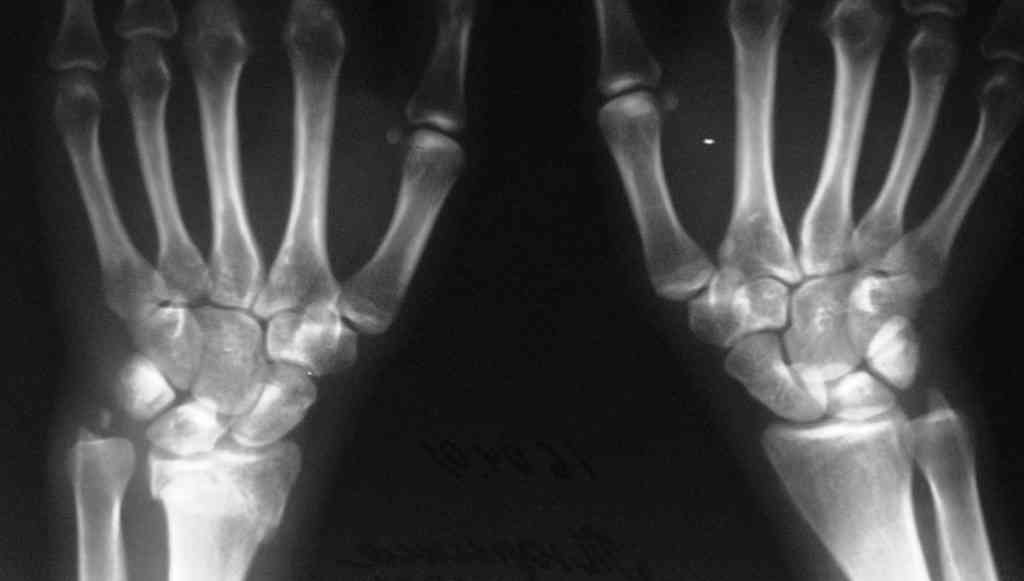

Судя по показанным Рг граммам, очевиден посттравм. артроз лучезапястного сустава, проблема дистального радиоульнарного сочленения(TFCC).

Угол наклона лучевой фасетки в норме в пределах 10-15 градусов, на представленном боковом снимке -может быть чуть больше 15градусов. Выполнив

разгибательную остеотомию луча, ты поставишь фасетку в нейтральное положение и таким образом увеличится угол разгибания , но уменьшится сгибание. По сути, амплитуда движений останется такой же.

Первым этапом я бы убрал пластину с последующей ограниченной резекцией головки локтевой кости(hemiresection and interposition arthroplasty Bowers technique). провести курс реабилитации. если уровень мобильности сустава не

будет устраивать больного, можно рассмотреть проксимальную карпальную резекцию в качестве последующего этапа.